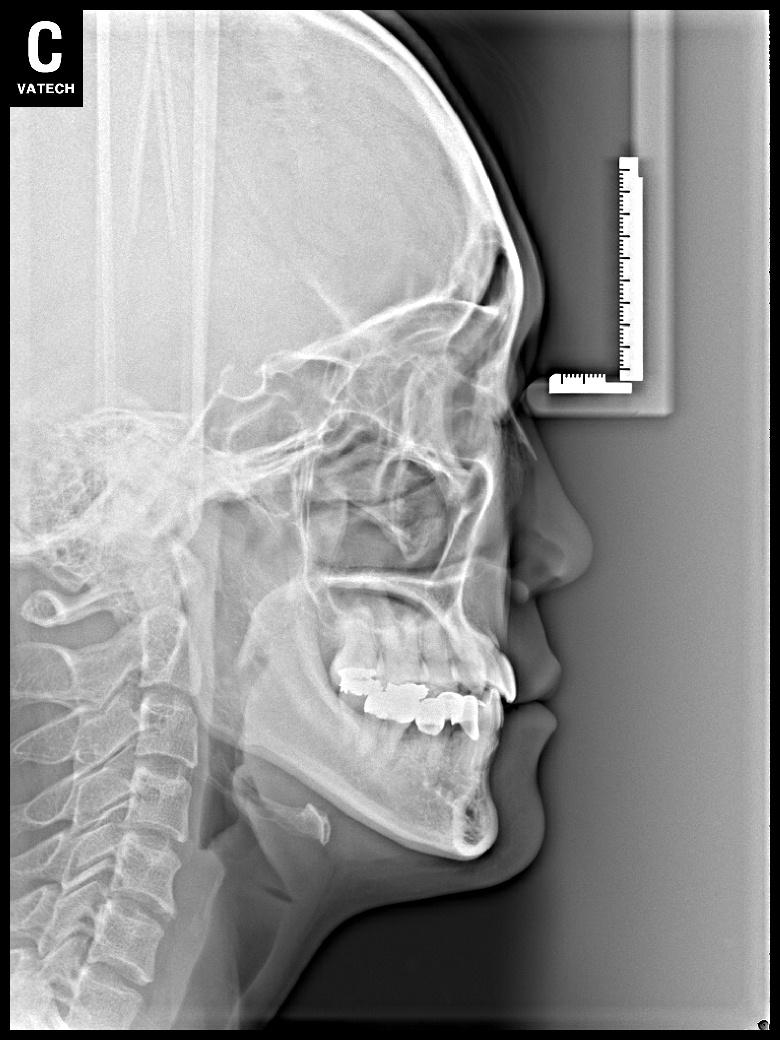

치료 전 사진입니다.